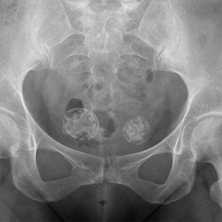

(Слева) КТ, аксиальная проекция, костный режим: случайно выявленный в крестце костный островок. Однородный склеротический очаг имеет типичные признаки угасания на периферии с переходом в сопряженную кость. Это может давать характерный несколько инфильтративный вид щетки или звездчатость.

(Справа) Сцинтиграфия, задняя проекция: у этого же пациента визуализируется фокальный округлый очаг накопления, соответствующий костному островку. При достаточно большом размере патологического очага, его склеротическая природа обусловливает позитивную сцинтиграфию. (Слева) КТ сканография: довольно крупный костный островок. Он имеет однородную плотность и расположен в костномозговом пространстве. У мужчины средних лет, как в данном случае, такая картина могла быть расценена как метастаз при раке предстательной железы.

(Справа) КТ, аксиальная проекция, без контрастного усиления: патологический очаг сливается с нормальной окружающей костью и имеет спикулы на периферии, типичные для костного островка. Не удивляйтесь, обнаружив, что при сцинтиграфии данное образование имеет вид горячего очага. Достаточно крупный эностоз характеризуется повышенным накоплением. (Слева) Рентгенография в ПЗ проекции, выполненная по причине боли в противоположном тазобедренном суставе: случайно выявленные склеротические очаги в левой подвздошной кости. При сцинтиграфии (не представлена) патологического накопления не выявлено. Тем не менее, такое необычное скопление склеротических очагов позволяет предположить наличие метастазов.

(Справа) КТ, аксиальная проекция: у этого же пациента определяются патологические очаги с заваренными краями, плотность которых соответствует кортикальной кости. Эти очаги оставались стабильными через четыре года и, поэтому, не требовали дальнейшего наблюдения. Они представляют собой необычное скопление эностозов.